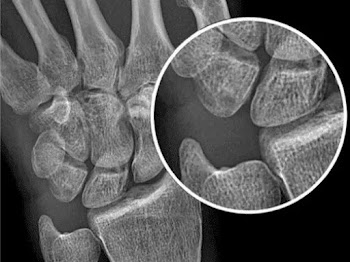

Computed Tomography, commonly known as CT or CAT scan, is a cornerstone of diagnostic imaging. Specialized computed tomography courses delve deep into this technology, covering everything from image acquisition to interpretation. These courses enhance your ability to create detailed cross-sectional images, aiding accurate diagnosis and treatment planning.